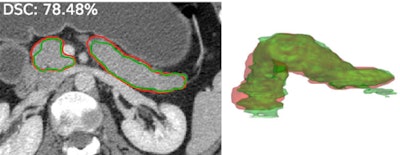

Pancreas detection and segmentation has recently taken off as well, according to Summers.

"We placed a training dataset on the internet along with annotations, and a number of groups have been picking up on this and advancing the status of the field quite rapidly, so we're now getting accuracies in the low- to mid-80th percentile for pancreas segmentation," Summers said. "I think this will have applications for tumor detection and analysis and diabetes."